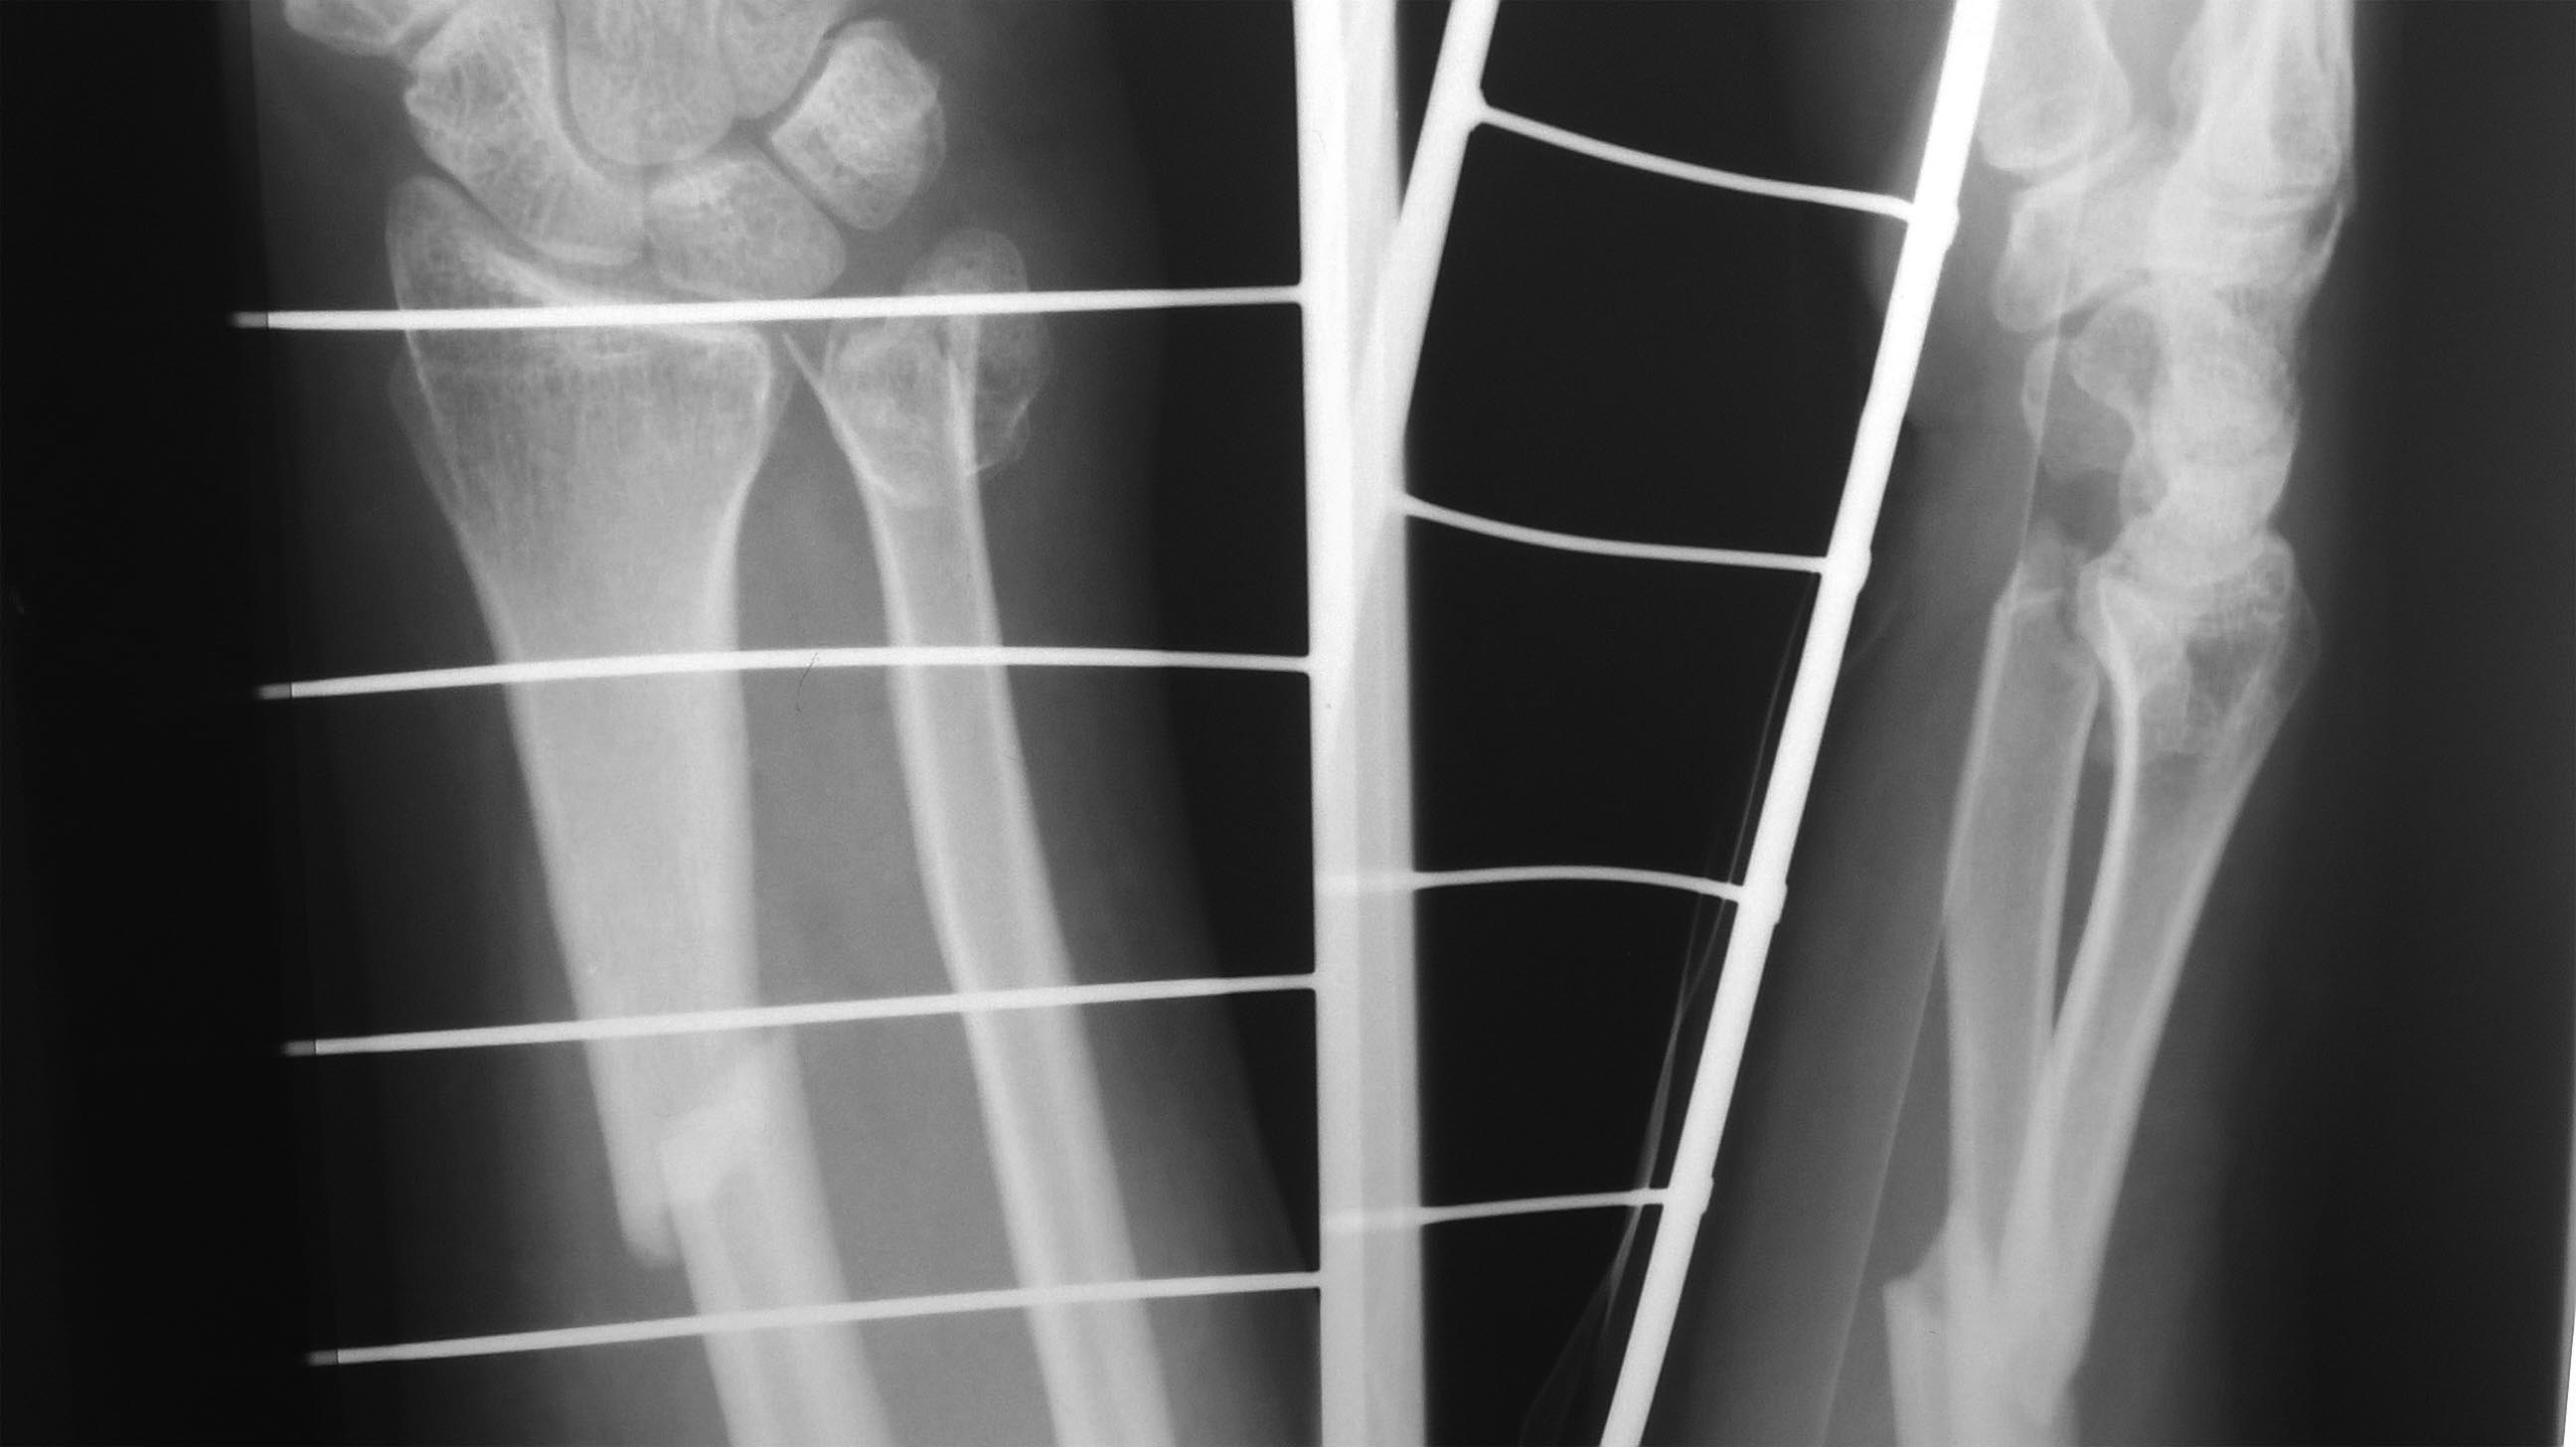

Re: перелом Galeazzi

спасибо за советы. Прошу прощения,но предоставил не полную информацию, не загрузилась первичная рентгенограмма по которой можно определить степень повреждения локтевой кости.